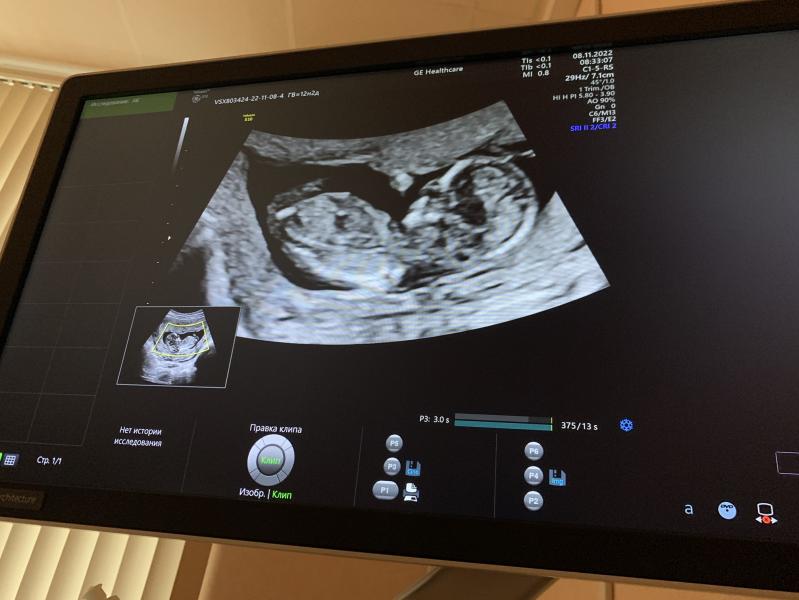

Беременность протекала на удивление легко. Никаких угроз, все с малышом было хорошо, были проблемы только с моими тромбоцитами. Они начали снижаться. Меня держали на особом контроле и я почти постоянно была в разъездах - каждую неделю сдавала анализы, была в женской консультации, перинатальном, в гематологии. Я ходила туда уже как к себе домой и моя неделя вся была расписана поездками. Кстати, за рулем я проездила до самых родов.